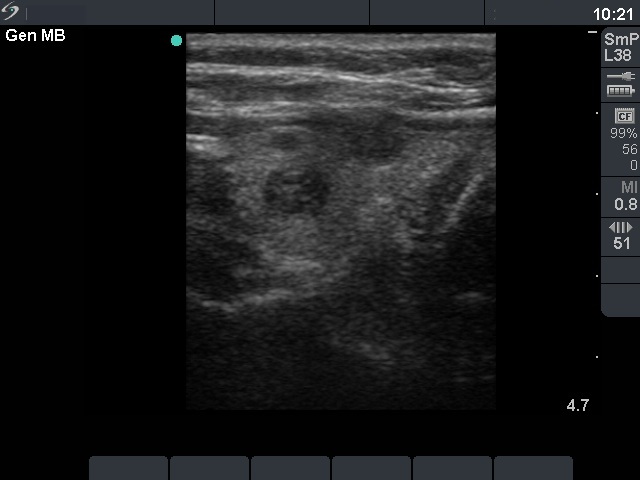

The role of complex diagnosis - follow-up of follicular lesions - Case 8. (ultrasonographic picture 6)

Left lobe, longitudinal scan.